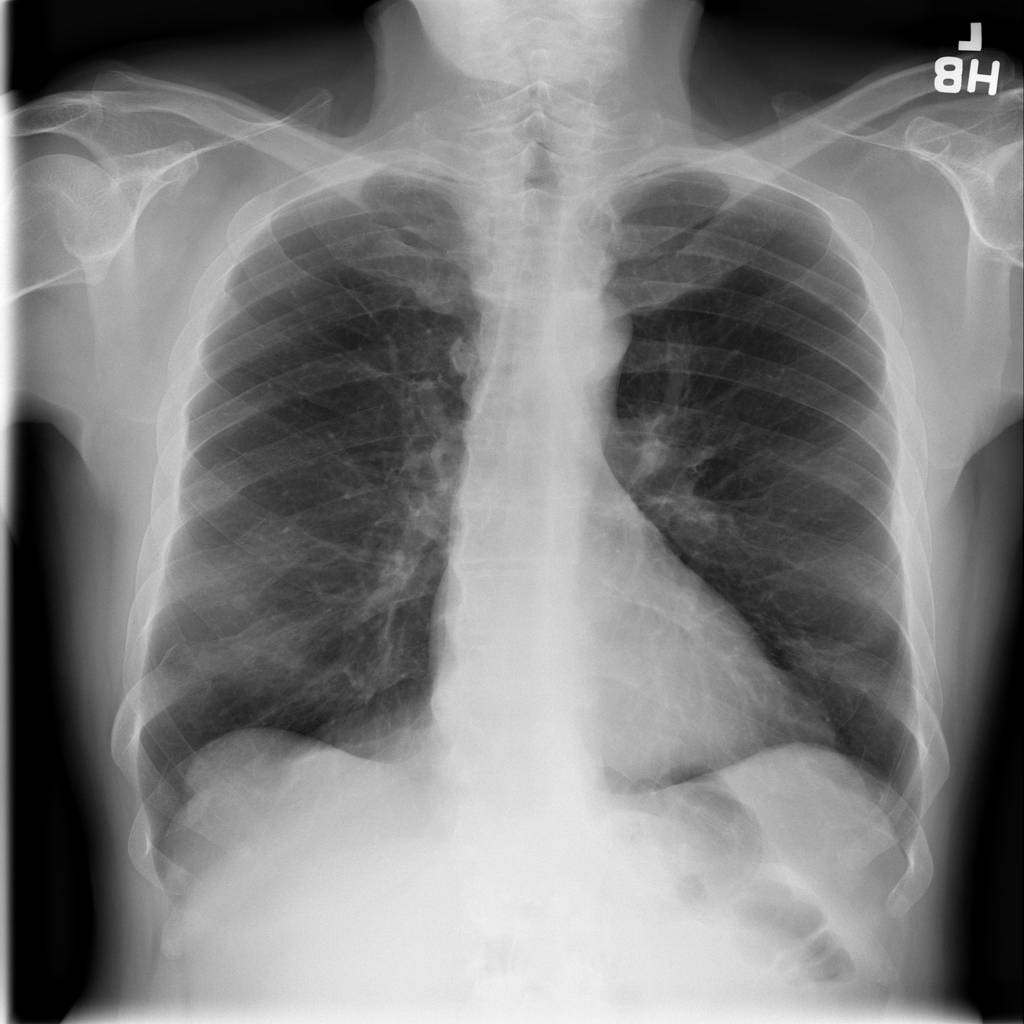

Nodule

A nodule is a small rounded opacity in the lung or chest field. It is a descriptive imaging finding that can be benign or more concerning depending on size, appearance, and context.

PAT-5857 · IMG-000Nodule

PAT-5857 · IMG-000

PA